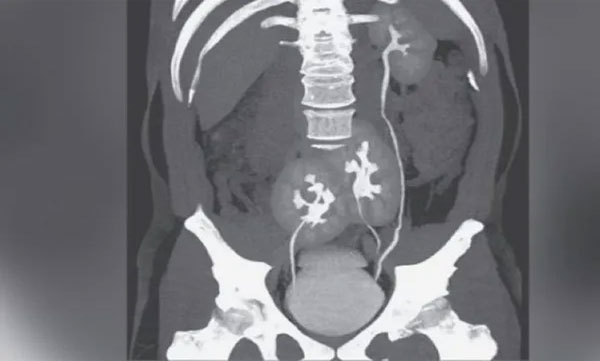

സാവോ പോളോ: അസഹനീയമായ നടുവേദനയുമായി ആശുപത്രിയില് ചികിത്സയ്ക്കെത്തിയ യുവാവിന്റെ സിടി സ്കാന് ഫലം കണ്ട് ശരിക്കും ഞെട്ടിയത് ഡോക്ടര്മാരായിരുന്നു. യുവാവിന് രണ്ട് വൃക്കകള്ക്ക് പകരം മൂന്ന് വൃക്കകള്!

ബ്രസീലിലെ സാവോ പോളോയിലെ ഡോ റിം ആശുപത്രിയിലാണ് സംഭവം. 38കാരനാണ് ചികിത്സ തേടി ഇവിടെയെത്തിയത്. നടുവ് വേദനയുടെ കാരണം കണ്ടെത്തുന്നതിനായി ഡോക്ടര്മാര് ഇയാളെ സിടി സ്കാനിന് വിധേയമാക്കി. ഇയാള് ഡിസ്ക് സ്ഥാനംതെറ്റിയ അവസ്ഥയിലാണെന്നും സാധാരണ ഗതിയിലുള്ള രണ്ട് കിഡ്നികള്ക്കൊപ്പം ഇടതുഭാഗത്ത് മുകളിലായി മറ്റൊരു കിഡ്നി കൂടിയൂണ്ടെന്നും കണ്ടെത്തി.

എന്നാല് ഇയാളില് വൃക്ക സംബന്ധമായ ഒരു രോഗലക്ഷണവുമുണ്ടായിരുന്നില്ല. ആ വൃക്കയും സാധാരണ രീതിയില് പ്രവര്ത്തിക്കുകയും ചെയ്തിരുന്നു. വൃക്കകളില് നിന്നും മൂത്രനാളി വഴി മൂത്രാശയത്തിലേക്ക് ബന്ധിപ്പിക്കുന്ന രണ്ട് സാധാരണ വൃക്കകള്ക്കൊപ്പം മൂത്രനാളിയിലേക്ക് ബന്ധിച്ചിരിക്കുന്ന അവസ്ഥയിലാണ് മൂന്നാമത്തെ വൃക്കയും. ദി ന്യൂ ഇംഗ്ലണ്ട് ജേര്ണല് ഓഫ് മെഡിസിന് ആണ് ഈ റിപ്പോര്ട്ട് പുറത്തുവിട്ടത്.